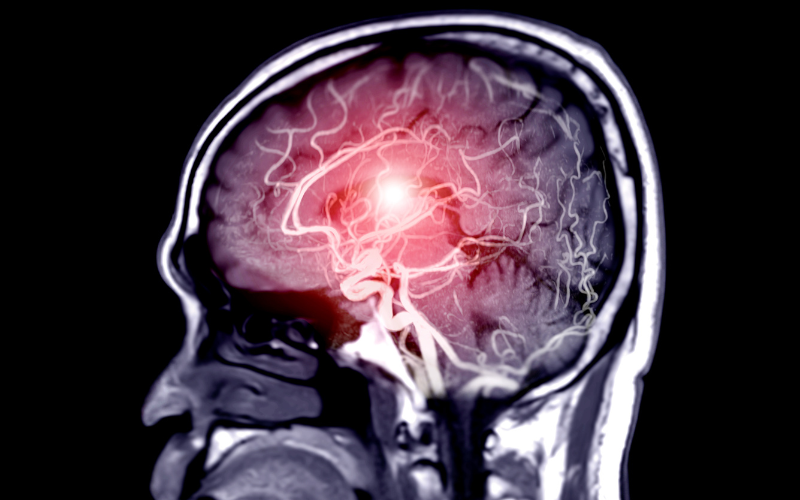

With increasing life expectancy and a growing elderly population, neurological disorders in older adults have become increasingly common. Geriatric Neurosurgery focuses on the diagnosis and management of age-related brain and spine disorders that often require delicate and precise surgical intervention. These conditions are challenging not only because of their complexity but also because elderly patients often have other health concerns that demand careful coordination and individualized treatment plans.

Older patients are often more susceptible to neurological issues due to degenerative changes, vascular fragility, and reduced physiological reserve. Geriatric neurosurgery aims not just to correct structural problems but also to improve functional independence, mental clarity, and overall quality of life. Every treatment is tailored to the patient’s overall health, mobility, and family support, ensuring that surgery provides tangible, lasting benefits.

The management of elderly patients with neurological or spinal disorders requires a holistic approach that extends far beyond surgery. Evaluation begins with a detailed assessment, including brain imaging, functional tests, and cognitive evaluations, to determine whether surgery will truly enhance the patient’s life and capabilities.

For brain-related conditions like Normal Pressure Hydrocephalus (NPH), Dr. Rahul Gupta employs endoscopic or shunt-based procedures that relieve fluid build-up, helping patients regain mobility, bladder control, and alertness. For vascular and hemorrhagic conditions, advanced micro-neurosurgical techniques and endovascular procedures are used to prevent further bleeding or stroke.